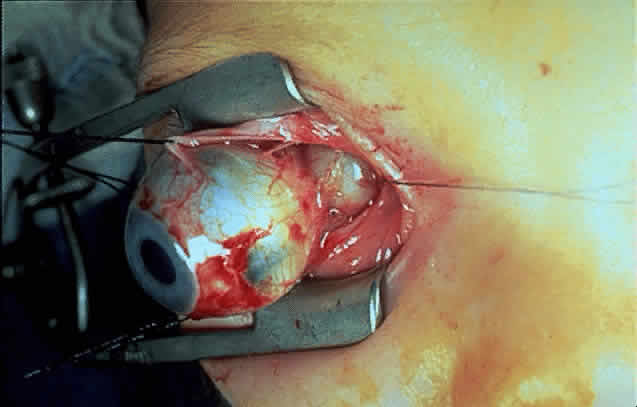

Gross examination of optic nerve gliomas usually reveals a smooth, fusiform, intradural enlargement of the optic nerve (Fig. 6). After extending through the optic canal in a dumbbell fashion, there may be extension to posterior structures.4 Most optic gliomas are classified as juvenile pilocytic astrocytomas and have a benign histologic appearance. Pilocytic refers to the spindle-shaped astrocytes with elongated nuclei that are often arranged in a parallel fashion (Fig. 7). Oligodendroglial cells may be scattered throughout the glioma. These tumors can contain carrot- or cigar-shaped eosinophilic astrocytic cytoplasmic inclusions known as Rosenthal fibers4 (Fig. 8). Microcystoid extracellular spaces containing acid mucopolysaccharide generated by mucin-producing astrocytes are often seen.85 Less common features can include capillary hyperplasia, mitotic figures, tissue necrosis with hemorrhage,86 and glial giant cells.4

Fig. 6. Operative photograph demonstrating optic nerve glioma. Note fusiform enlargement of the optic nerve sheath. (Courtesy of Terry L. Schwartz, MD)